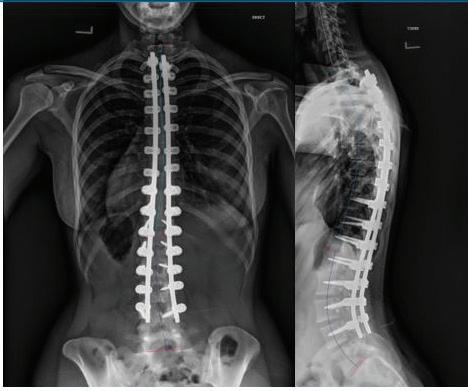

28. Cleveland Clinic. Atropine eye solution.[Internet]. Cleveland, OH: Cleveland Clinic; 2024[cited 2024 Nov 17]. Available from https://my.clevelandclinic. org/health/drugs/20729-atropine-eye-solution

29. Mayo Clinic. Neomycin, polymyxin b, and dexamethasone (opthalmic route). [Internet]. Rochester, MN: Mayo Clinic; 2024[cited 2024 Nov 17]. Available from https://www.mayoclinic.org/ drugs-supplements/neomycin-polymyxin-b-anddexamethasone-ophthalmic-route/description/ drg-20406312#

30. Im K, Mareninov S, Diaz MFP, Yong WH. An introduction to performing immunofluorescence staining. Methods Mol Biol. 2019:1897:299-311

31. Cross N, Steen CC, Zegaoui Y, Satherley A, Angelillo L. Current and future treatment of retinitis pigmentosa. Clin Opthalmol. 2020; 16:2909-2921

32. Musarella MA, Macdonald IM. Current concepts in the treatment of retinitis pigmentosa. J Opthalmol 2011:2011:753547

33. Hamel C. Retinitis pigmentosa. Orphanet J Rare Dis. 2006;1:40